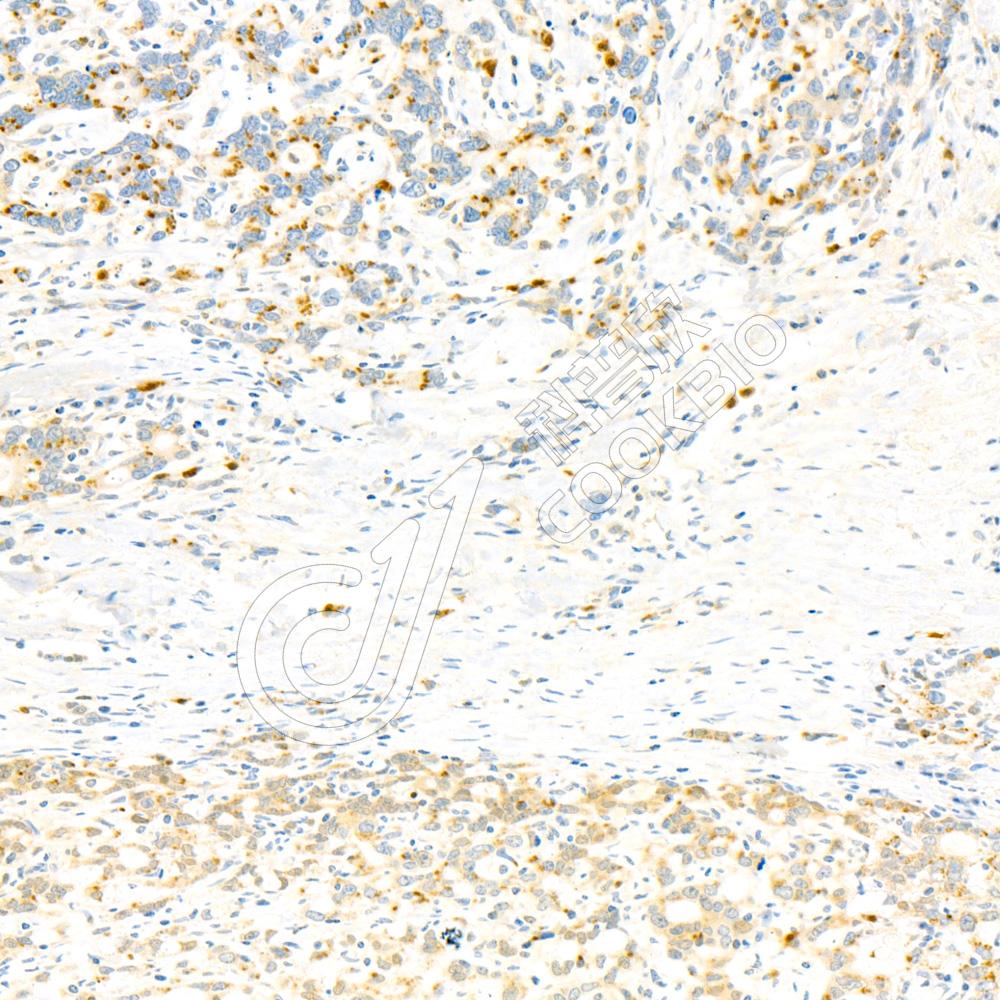

IHC检测NBR1蛋白(货号 K135364).

样品: 人结肠癌, 4%多聚甲醛 (货号KSG1101) 固定12-24小时.

抗原修复: 柠檬酸抗原修复液(干粉, pH 6.0) (KSG1201), 98℃, 20分钟.

—抗: 1: 2300稀释, 4℃ 孵育过夜.

二抗: S-vision免疫组化多聚二抗(山羊抗兔),即用型 (货号KB3906), 室温孵育20分钟.

样品: 人胃癌, 4%多聚甲醛 (货号KSG1101) 固定12-24小时.